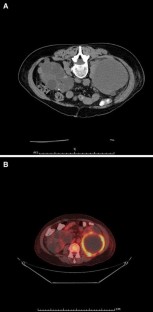

Fig. 1